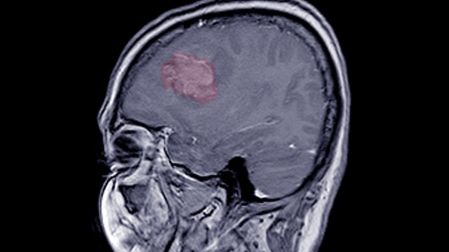

En 2015, Kate Walsh fue diagnosticada con un meningioma, un tumor cerebral del tamaño de un limón. Aunque en un principio no notó síntomas alarmantes, con el tiempo empezó a experimentar señales que indicaban que algo no estaba bien.

Fue en ese momento cuando los especialistas detectaron el meningioma en el lóbulo frontal izquierdo de su cerebro.

El Instituto Médico Mayo Clinic explica que el meningioma es un tipo de tumor que crece en las membranas que rodean el cerebro y la médula espinal.

Aunque técnicamente no es un tumor cerebral, puede ejercer presión sobre el cerebro, los nervios y los vasos sanguíneos cercanos, causando síntomas diversos dependiendo de su tamaño y ubicación.

En la mayoría de los casos, los meningiomas crecen lentamente a lo largo de los años, por lo que pueden pasar desapercibidos hasta que comienzan a afectar las funciones neurológicas. Entre los síntomas más comunes se encuentran: